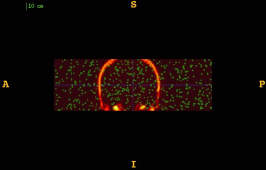

Figure 1 shows the examples of pixel selection masks generated using tested approaches at the highest resolution level for pixel sampling rate 0.5%. It is obvious that the samples generated with the URS approach are extremely spread, whereas the samples generated with the GMS approach are overly concentrated along the gradient magnitude structures present in the image. The proposed approach produces samples that balance those two extremities.